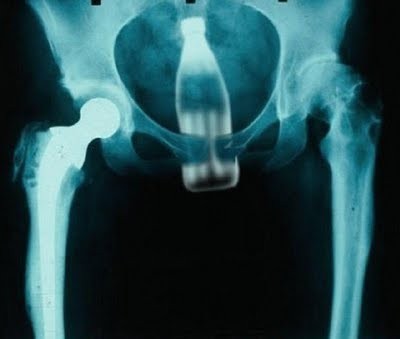

Одним из лидеров недели в Twitter стал хештег #WeirdThingsToPutUpYourAss (Странные штуки, которые суют в задницу). Проктологи со всего мира поделились рентгеновскими снимками содержимого анусов своих пациентов. Выяснилось, что огурец - еще не самое удивительно, что можно обнаружить там, где не светит солнце.